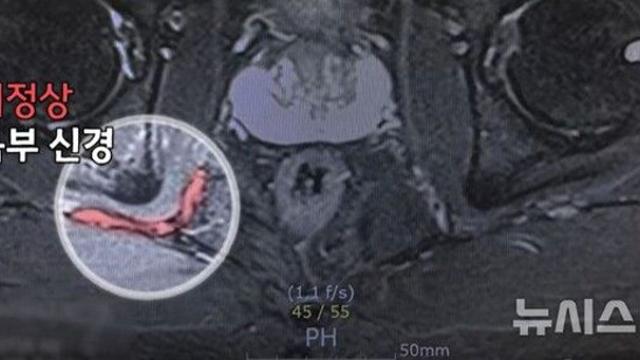

병명 몰라 40년간 병원 전전한 60대…"일상 되찾아 감사"

모두서치 2025.08.26

사진 = 뉴시스   춘천에 거주하는 68세 박근화(가명)씨는 1986년 군 전역 직후 갑작